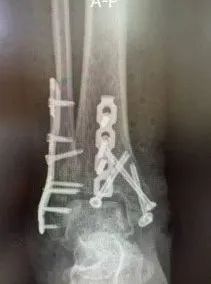

在李涛教授的建议下,最终创伤骨科团队决定采取俯卧位踝关节后外侧联合内侧入路的方式,将腓骨钢板、后侧支撑钢板以及空心螺钉一并植入进行手术固定治疗,并由李涛教授上阵操刀手术。

经过充分的术前准备,在李涛教授细致熟练的手术操作和麻醉团队的密切配合下,李涛教授主刀开展手术创伤骨科团队顺利为米热完成了腓骨、内踝、胫骨远端后方骨折断端的松解、清理、复位及固定,手术效果良好。